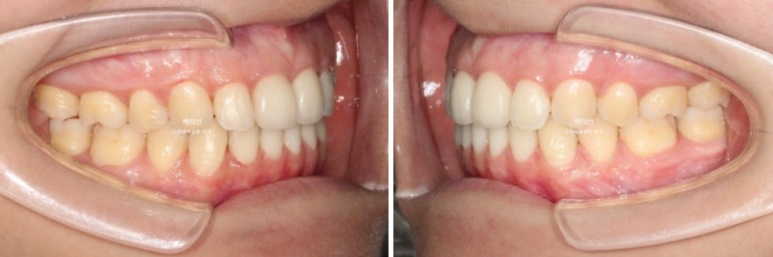

25.06

25년 3월부터 25년 6월까지 인비절라인 장치 14개를 다 낀 후 모습입니다.

중심선을 잘 맞아졌으며

남아있던 발치공간도 깔끔하게 사라졌습니다.

인비절라인라이트는 추가장치 제작의 기회가 1번 있지만 경과가 좋아 재제작 없이 치료를 마무리 하였습니다.